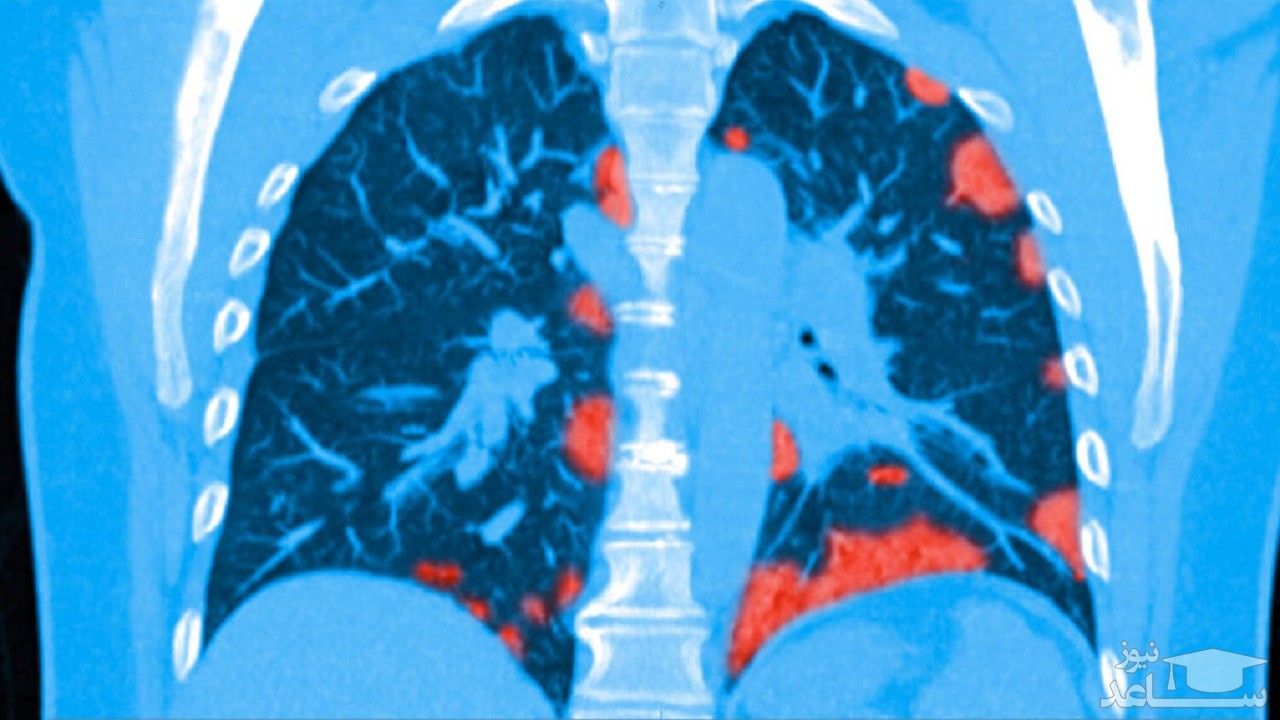

یووهی وانگ، (Yuhui Wang) رادیولوژیست در دانشگاه علم و فناوری Huazhong در ووهان چین گفت: این آسیب ها به دلیل وجود انبوهی از بافت های سفت شده است که باعث انسداد رگ های خونی در کیسه های ریز هوایی به نام آلوئول ها می شود. آلوئول ها اکسیژن را جذب می کنند تا ضایعات بافت اطراف خود را تشکیل دهند.

ضایعات بافتی می تواند نشانه مزمن بیماری های ریوی باشد، از جمله در بیماری سارس و مرس صدمات مشابهی در بیماران بهبودیافته مشاهده شده بود.

یک پاسخ ایمنی بیش فعالی ممکن است دلیل ایجاد جای زخم در ریه ها باشد، هجوم ناگهانی مولکول هایی به نام سیتوکین ها باعث التهاب ریه می شود و می تواند به بافت ریه آسیب برساند و آلوئول ها را پر از چرک کند.

در بدترین حالت، آسیب ناشی از این التهاب به حدی شدید است که در نهایت باعث ایجاد بافت ضخیم زخم می شود، چیزی که در سارس و مرس نیز دیده می شود.